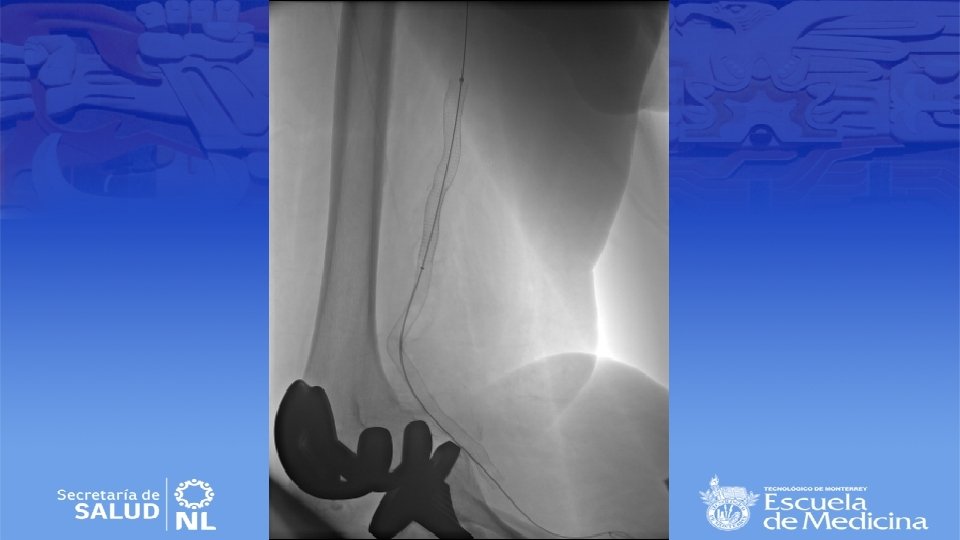

Impresión Diagnóstica • IDX: Aneurisma Poplíteo bilateral

Diagnostico • Ultrasonido Doppler, Angiotac, angioresonancia • Arteriografía es mas apropiada para sintomatología aguda